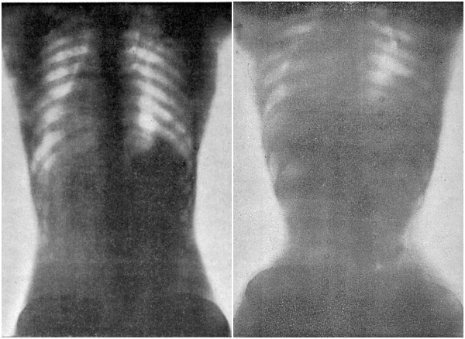

In questa foto d’epoca, il prima e dopo di una donna col corsetto: